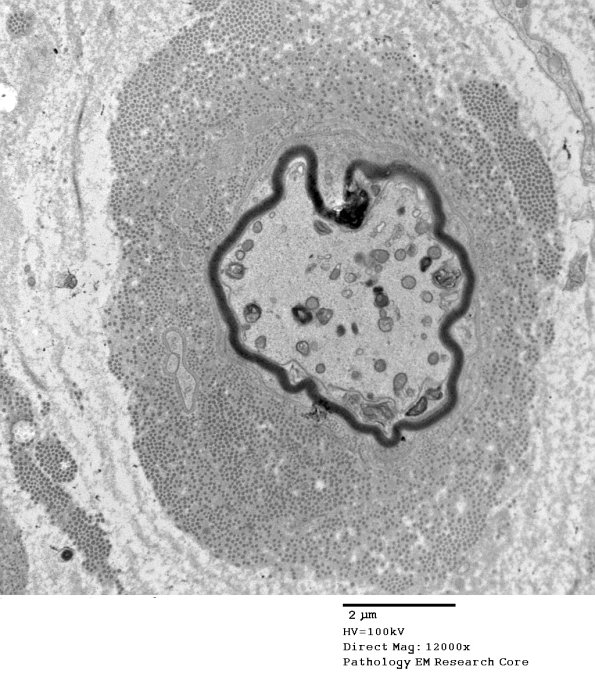

A similar process involves this thinly myelinated axon with accumulated axonal cytosomes. (electron micrograph)